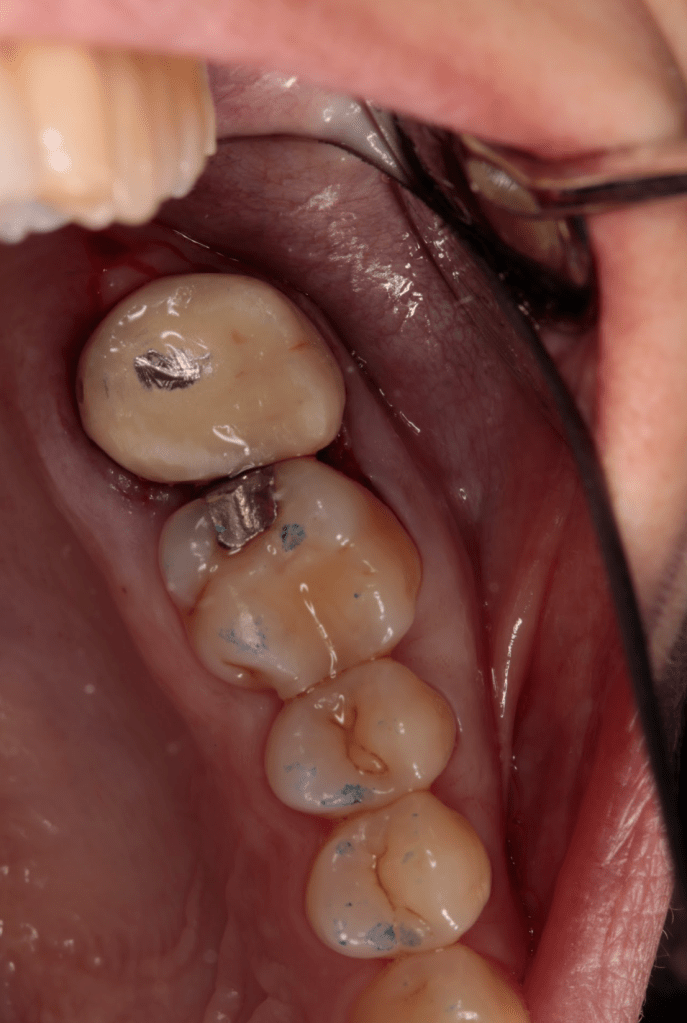

Fisura, remoción amalgama para explorar